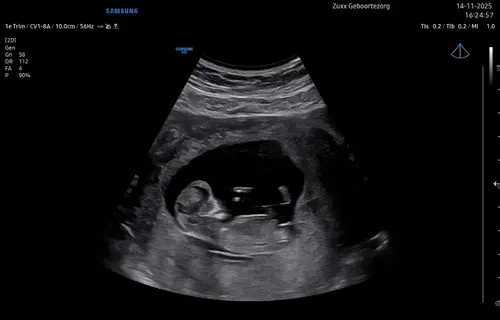

Hoi hoi! Hier 13+4 zwanger en vandaag 13 weken echo gehad. Dit is de enige foto van de zijkant want ons kindje was steeds aan het draaien haha. Heel benieuwd of jullie iets kunnen zien. Groetjes!

Hoi hoi! Hier 13+4 zwanger en vandaag 13 weken echo gehad. Dit is de enige ...